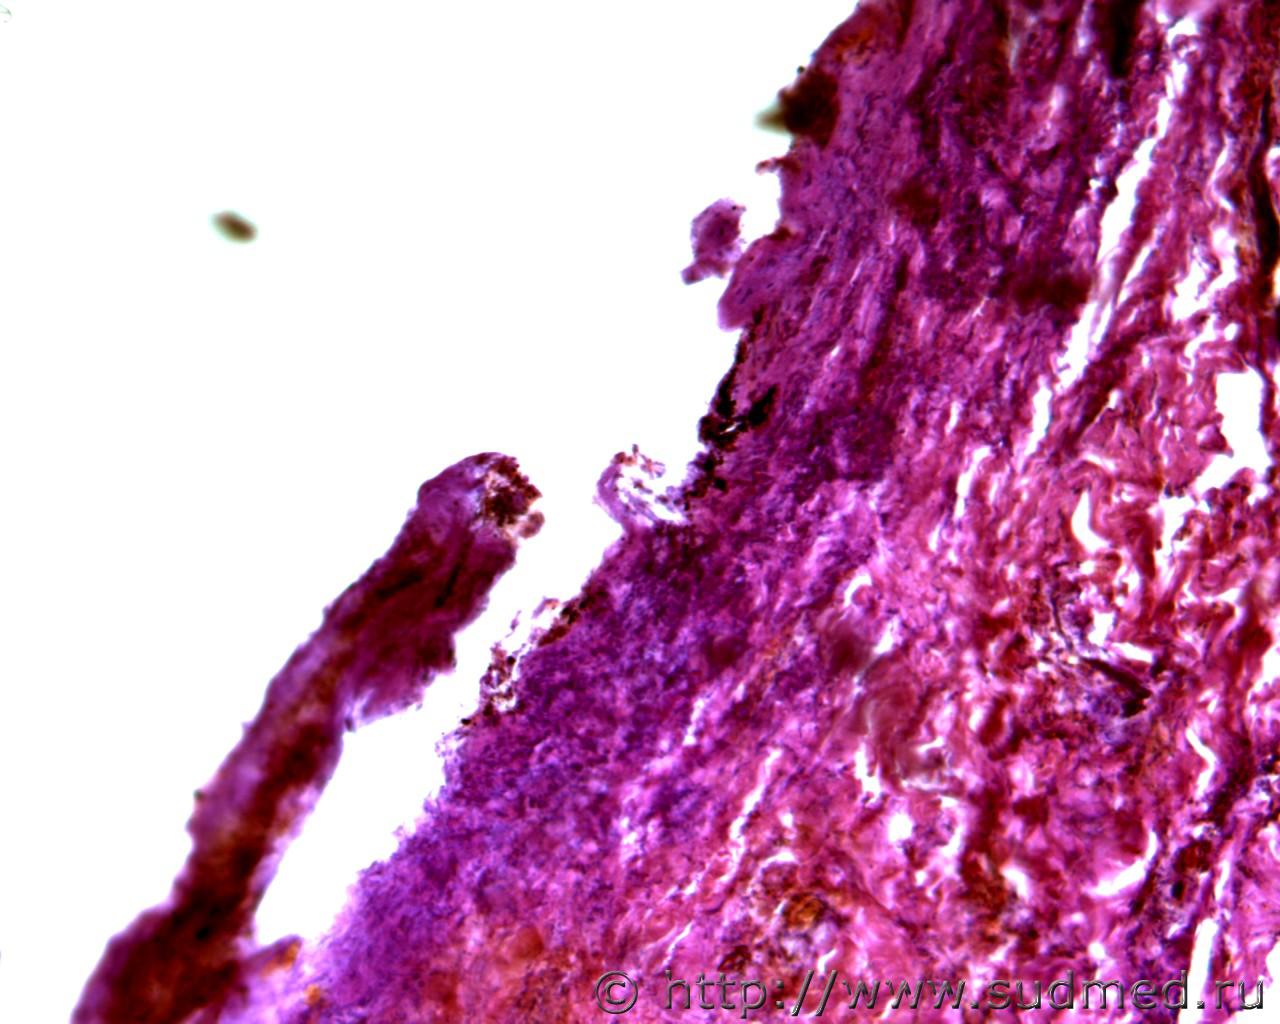

Мягкая странгуляционная борозда кожи шеи при удавлении петлей(скотч), М.32 года.На фото 1 нормальные участки, далее прерывистые обрывки эпидермиса и уплощение, сглаживание сосочкового слоя, кровоизлияние в подкожной клетчатке. Очаги острой эмфиземы в легких.